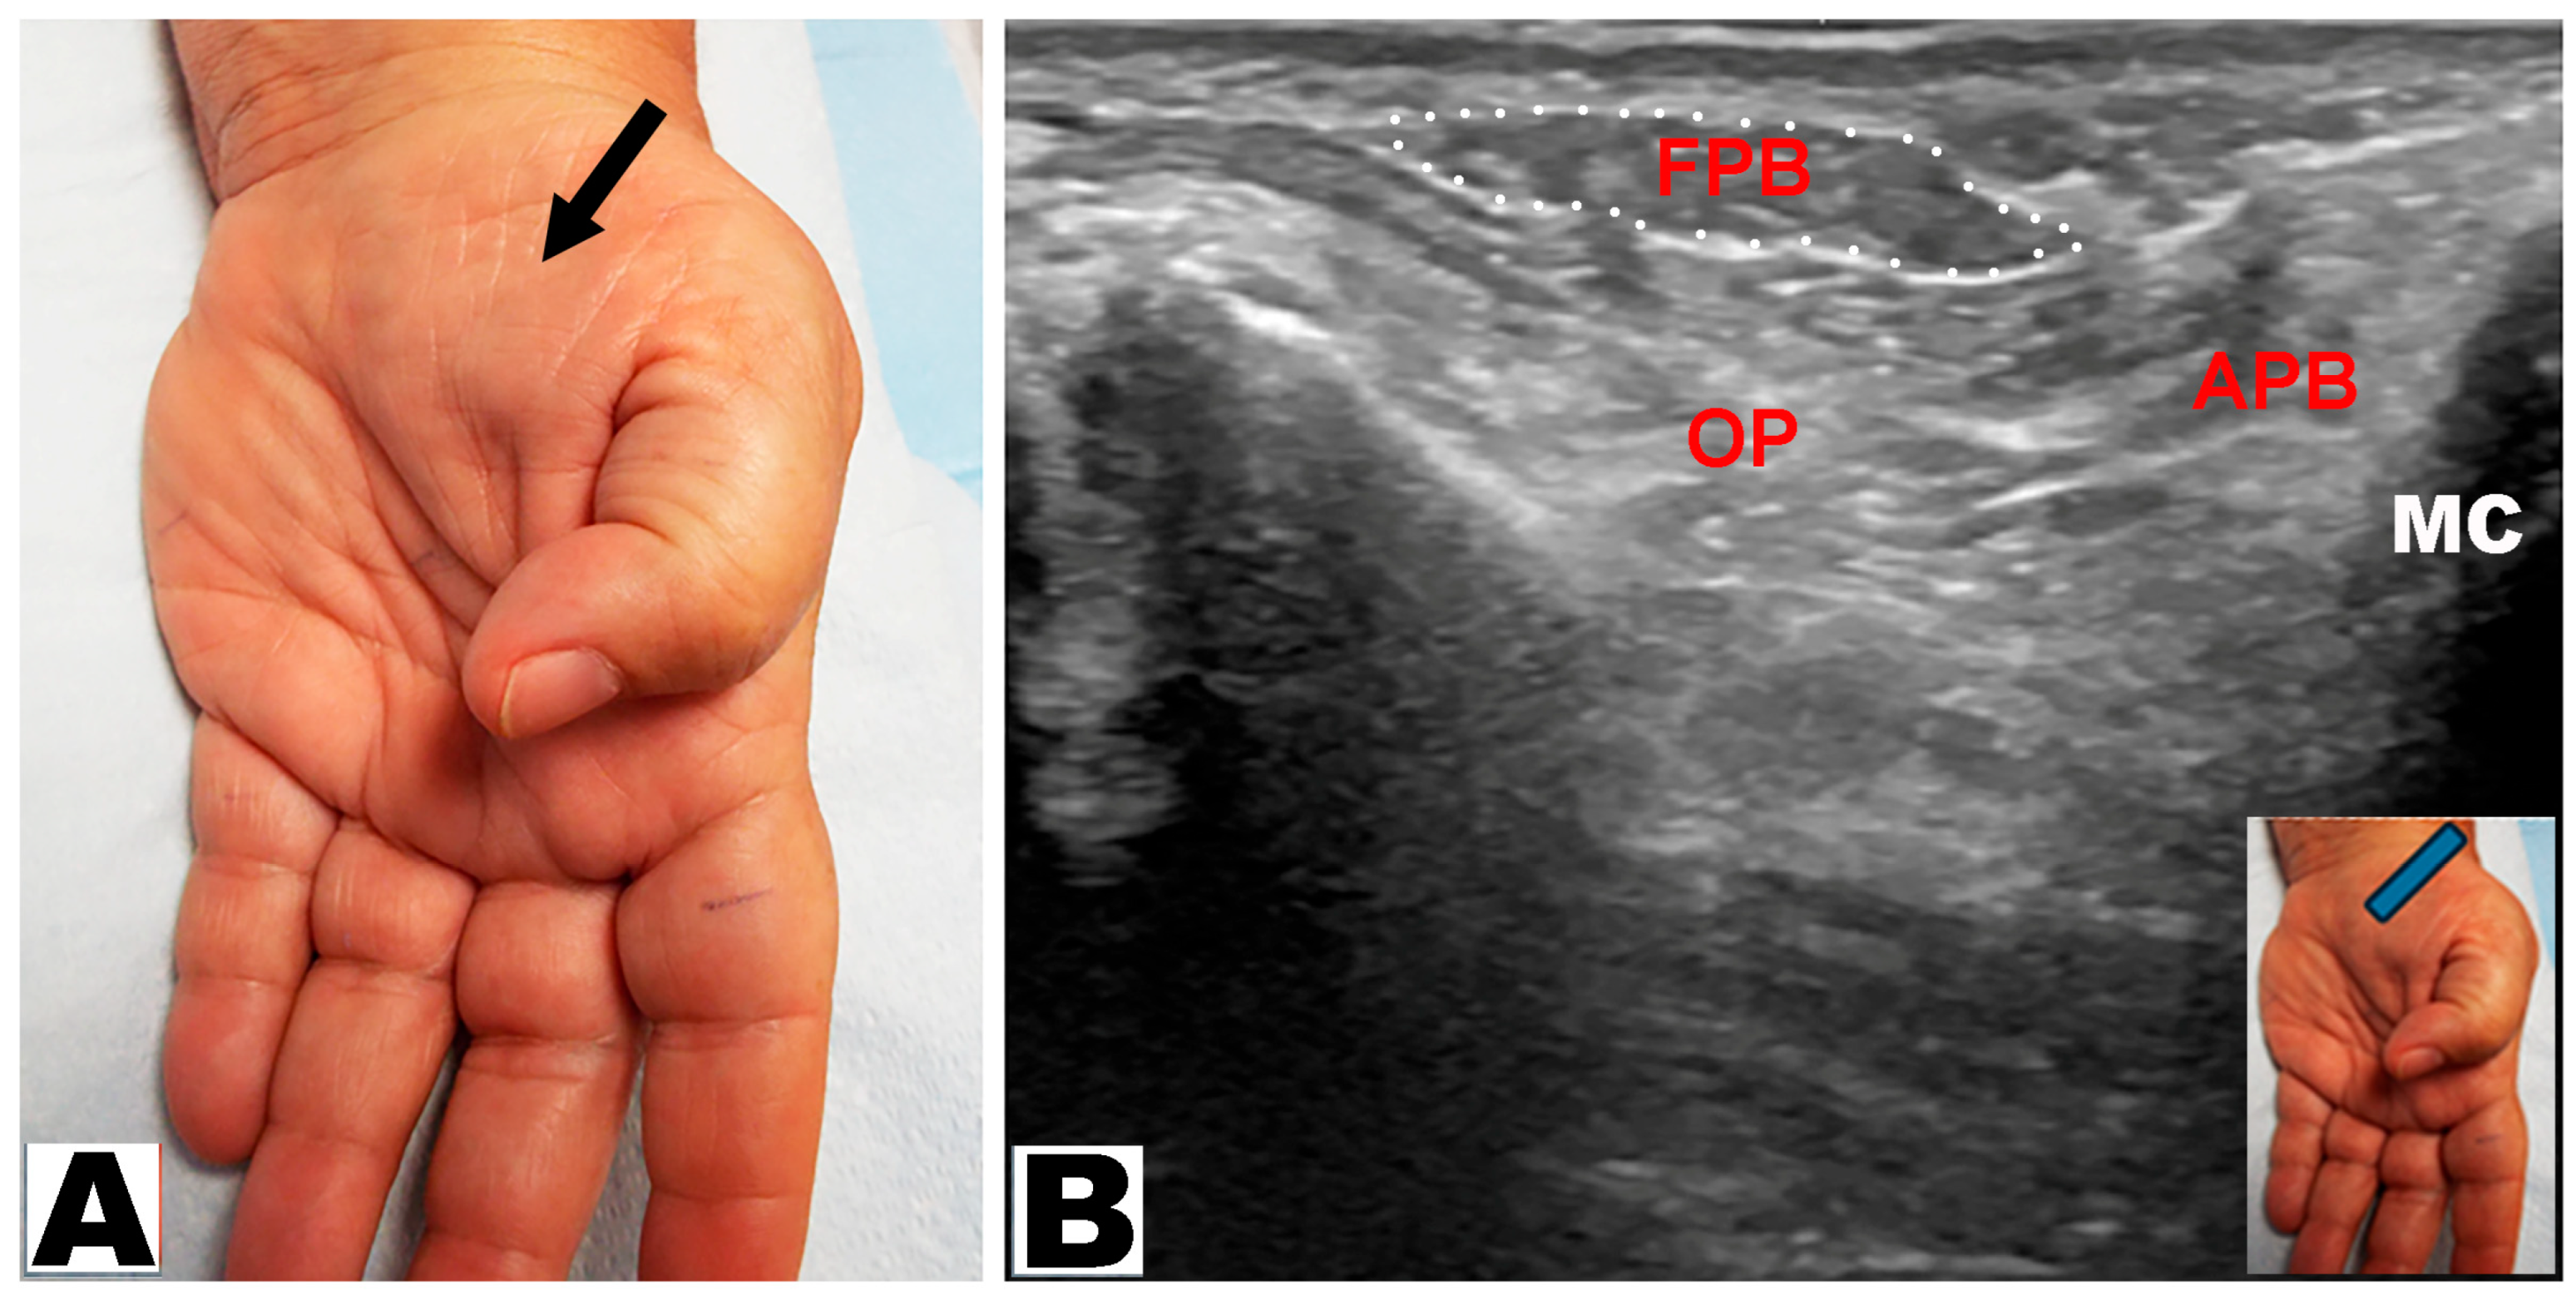

| Partial | APB and OP muscles are atrophic with an intact FPB muscle visible in the distal/medial part of the thenar eminence | 1. Severe CTS with intact deep head of the FPB (innervated by the ulnar nerve) |

| 2. Severe CTS with an intact FPB muscle due to ulnar innervation of both heads | ||

| Partial with hypertrophy of the FPB | APB and OP muscles are atrophic, causing the lateral part of thenar eminence to be flat with a prominent “bulge” on the medial aspect from a large FPB muscle | Severe CTS with an intact FPB muscle compensating for the loss of the OP muscle; more likely when the FPB muscle is entirely supplied by the ulnar nerve |